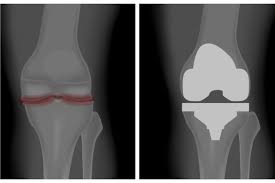

무릎 인공관절 수술, 왜 필요한가요?

무릎관절은 체중을 가장 많이 지탱하는 관절입니다. 나이가 들수록 연골은 점차 마모되고, 충격을 흡수하는 능력도 감소합니다. 이로 인해 통증, 뻣뻣함, 운동 제한이 생기며, 이런 증상이 악화되면 인공관절 수술이 필요해집니다.

퇴행성 관절염 외에도 류마티스 관절염이나 외상 후 관절 손상이 심각할 경우 수술이 권유되며, 수술을 통해 환자는 통증 없이 보행이 가능해지고 일상생활로 복귀할 수 있게 됩니다.